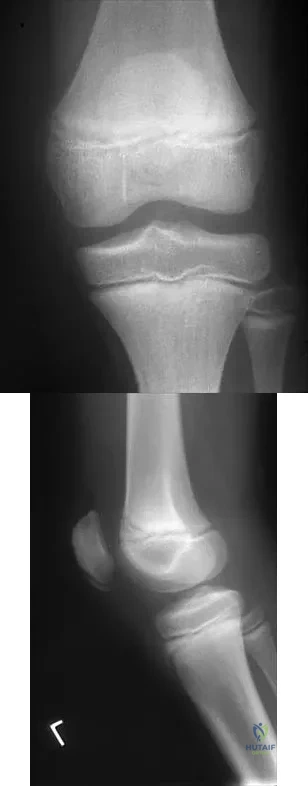

Question 42

Figures 10a and 10b show the radiographs of an athletic 9-year-old boy who has activity-related anterior knee pain with intact active knee extension. Examination reveals tenderness to palpation over the inferior pole of the patella. There is no effusion or ligamentous instability. Initial management should consist of